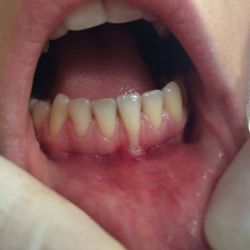

Especialización dedicada al cuidado de las encías. En este caso, se ha realizado un injerto de conjuntivo en el incisivo central inferior